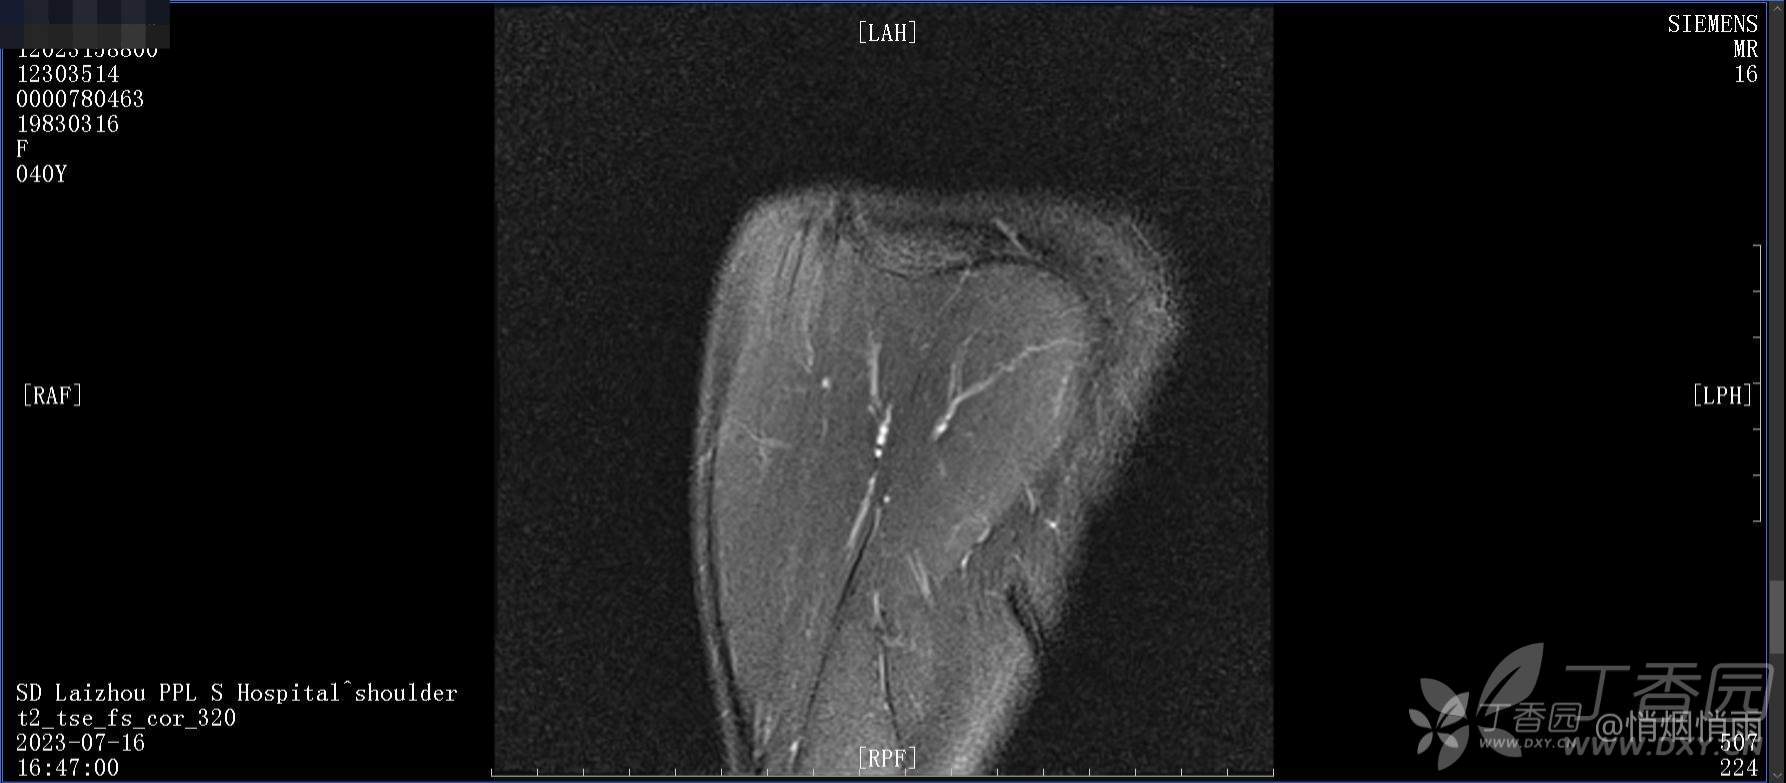

查体:右肩关节局部轻度肿胀,肩胛区压痛明显,痛处不固定,肩关节痛性活动受限,jobe test(+),lift -off test(+),中指、环指感觉较余指减退,余肢端感觉及血运情况可。

目前的诊断,暂时依据辅助检查诊为肩袖损伤,但是患者疼痛的性质和特点,却不是单纯的肩袖损伤所致。考虑过胸廓出口综合征,但是该疾病会出现肩胛区的疼痛吗?(由于考虑到费用的问题,没再进行下一步的检查)带状疱疹会有如此的症状吗?